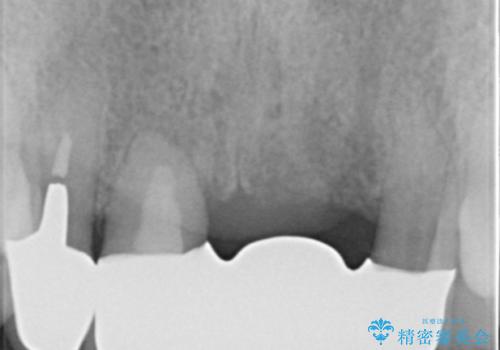

- 上下の前歯が抜けそうだとのことで来院されました。

精査したところ、動揺の著しい上下の前歯は重度の歯周病により保存不可能と判断しました。

ブリッジ、インプラント、義歯の選択肢の中で上下前歯ともにブリッジをご希望されました。

抜歯後歯肉の治癒を十分に待ったのち、ブリッジによる補綴治療を行いました。

歯周病が重度であったため抜歯後の歯肉の陥凹が大きく、GBRや歯肉移植による歯周組織の再建をおすすめしましたが、ご希望されませんでした。